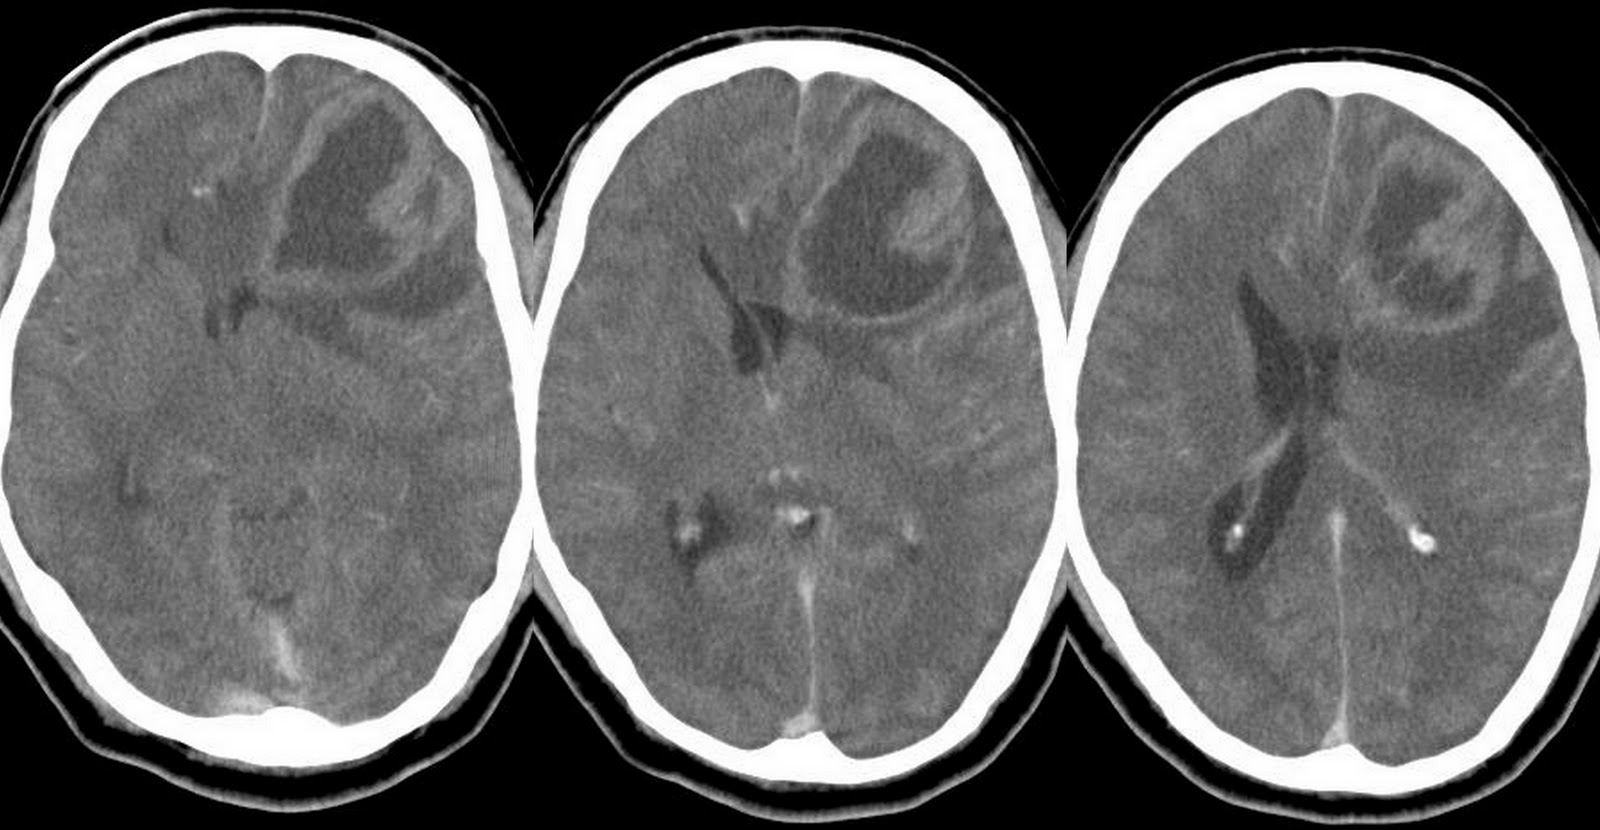

Glioblastoma (gbm) is the most common and aggressive malignant brain tumor in adults. Even when it appears a tumor has been eliminated with treatment, there is a high chance it will return. It is one of the most lethal forms of brain cancer.

It is characterized by microvascular endothelial proliferation and central necrosis.current standard treatment of glioblastoma consists of maximal safe surgical resection with adjuvant radiotherapy and chemotherapy with. Researchers are evaluating the optune device, along with chemotherapy for pediatric treatment. Glioblastoma (also known as glioblastoma multiforme or gbm) is the most aggressive type of tumor that arises in the brain.

“surgery within a few days of imaging or of presenting symptoms — to remove as much of the tumor as possible — is the first treatment for the majority of. Glioblastoma (gbm) is the most common primary malignant brain tumor in adults. The first treatment for glioblastomas is usually neurosurgery.